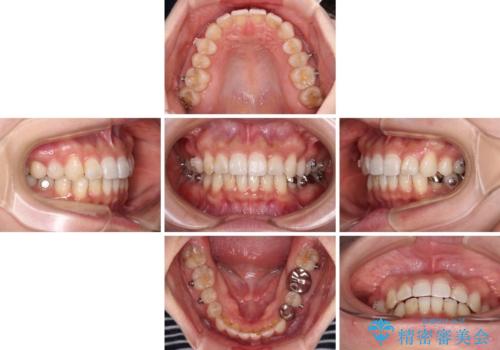

- 前歯のデコボコと深い咬み込みを気にして来院された患者様です。

インビザラインを用いて、前歯の叢生を解消するとともに、深い咬み合わせ(ディープバイト)を改善していくこととしました。

奥歯を後方に直立させることで深い咬み合わせを改善を図り、隠れていた下顎前歯が見えるほどになりました。